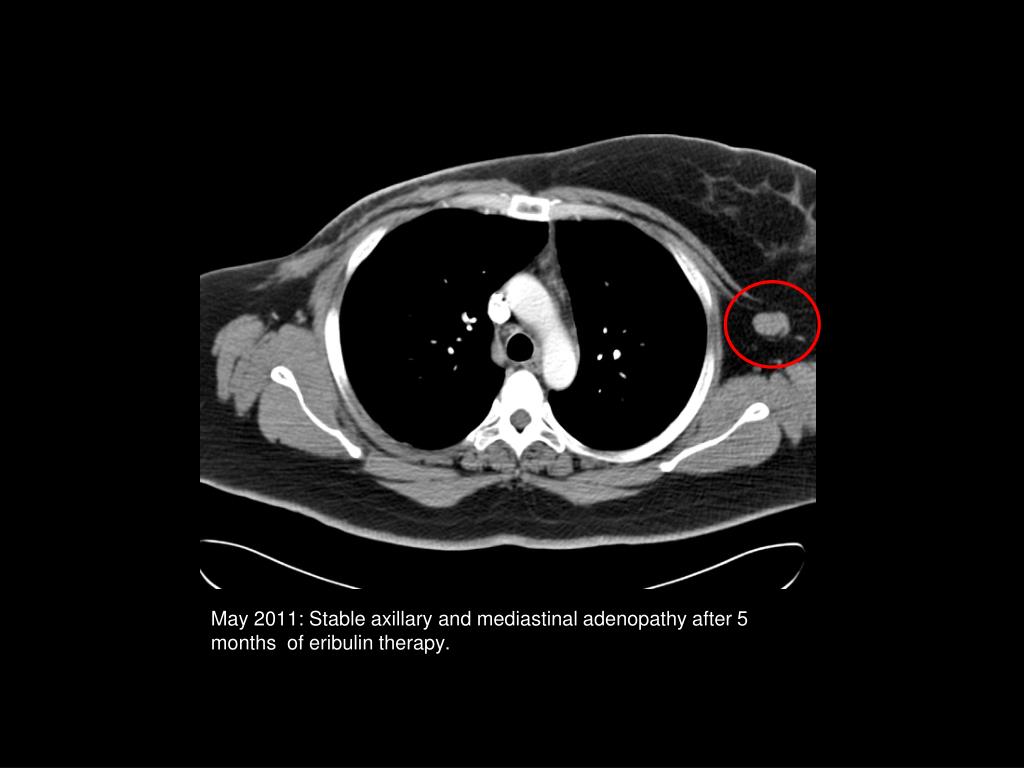

38. May 2011: Stable axillary and mediastinaladenopathy after 5 months of eribulin therapy.